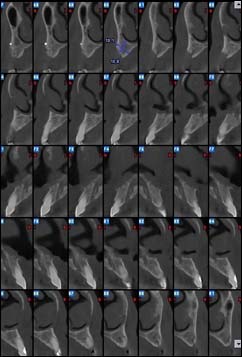

Examens tomographies volumiques type Scanner ou Cône beam

Dernière technologie à notre disposition, cette technique permet de voir en 3 dimensions des images de votre bouche et de mettre en évidence des pathologies ou des anomalies que les autres techniques ne permettent pas d’objectiver.

Coupe axiale

Reconstruction panoramique

Reconstruction coronale